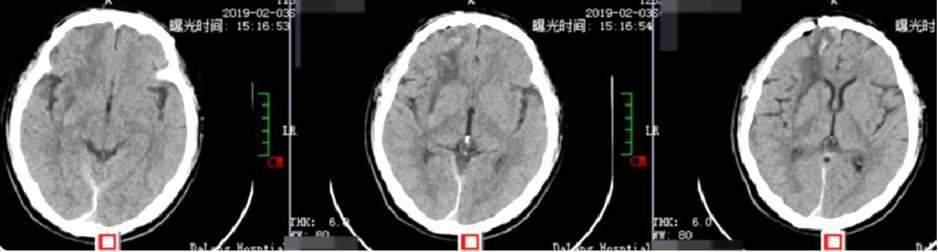

术后第一天

术后第1天